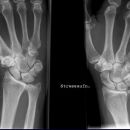

Handgelenk a.p.

Beurteilungskriterien

• Neigung der distalen Radiusgelenkfläche in der Frontalebene: 15 – 35°

• Längenverhältnis Radius – Ulna: Proc.styloideus radii überragt Gelenkfläche der Ulna um 9 –12mm (<9mm Ulna-Plusvariante, >12mm Ulnaminusvariante)

• Kontinuität der drei Karpalbögen:

Proximaler Bogen: proximale Gelenkflächenkonturen von Scaphoid, Lunatum und Triquetum

Mittlerer Bogen: distale Gelenkflächenkonturen von Sacphoid, Lunatum und Triquetum

Distaler Bogen: proximale Gelenkflächenkonturen von Capitatum und Hamatum

Fehlende Abgrenzbarkeit, Versatz oder Unterbrechung sind als pathologisch zu bewerten und deuten auf eine Luxation hin.

Trapezförmige Darstellung des Lunatum in Neutralstellung? Augenzeichen des Hamulus? Superposition von Pisiforme und Triquetum? Metacarpale III in Projektion innerhalb der Radiusgelenkfläche? Lunatum zu >50% über Radiusgelenkfläche? Cave: bei Radial- oder Ulnarduktion wandert das Lunatum in umgekehrter Richtung.

• M-förmiger Verlauf der Gelenkspalten der Carpometacarpalgelenke? Luxationsstellung in den Carpometacarpalgelenken (meist dorsale Luxation)?

• Gelenkspaltweiten des Radiocarpalgelenk 2 – 2,5mm, der Carpometacarpalgelenke 1 –2mm, distales Radioulnargelenk 2mm, Gelenksspaltweiten der Intercarpalgelenke 1,5 – 2mm

Cave: SL-Dissoziation (Ruptur des SL- Bandes, häufigste Gefügestörung): Terry-Thomas-Sign = SL-Spalt > 3mm, Siegelringzeichen = Ringförmige Transparenzminderung im mittleren Scaphoiddrittel durch orthograde Projektion der Taille infolge Rotation.

• Obliteration des Scaphoidfettstreifens?

• Täuschungsmöglichkeiten durch Vielzahl akzessorischer Ossikel (abgerundete, zirkulkär-geschlossene Kortikalis), geteilte Handwurzelknochen (Scaphoid, Lunatum, Pisiforme) und Gefäßkanälchen

• Target areas leicht zu übersehender Frakturen: distales Radioulnargelenk, Processus styloideus radii et ulnae, Basen der Metacarpalia (v.a. MCP I), Hamulus.

• Grundsätzlich gilt: unklare Verhältnisse ->CT-Indikation